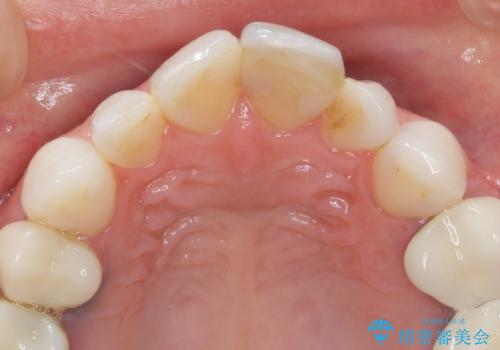

ラミネートベニヤの破折 ジルコニアクラウンによるやり替え

- 欠けてしまった前歯のラミネートベニヤと見た目の改善を求めて来院されました。

歯の大きさの不揃いと、虫歯の再発を認めたためラミネートのやりかえではなく一挙に問題の解決のできるジルコニアクラウンでの治療を計画します。

歯の大きさの不揃いが改善されただけでなく、色調もよくなり審美性をしっかりと改善することができました。